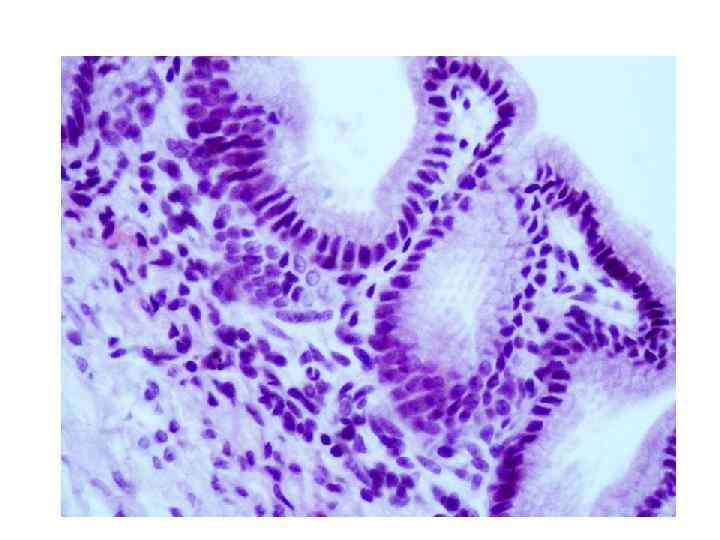

Ацинус и вставочный проток поджелудочной железы

Ациноциты и центроацинозная клетка

Ациноцит поджелудочной железы

Вставочный и межацинарный протоки поджелудочной железы

Зимогенные гранулы